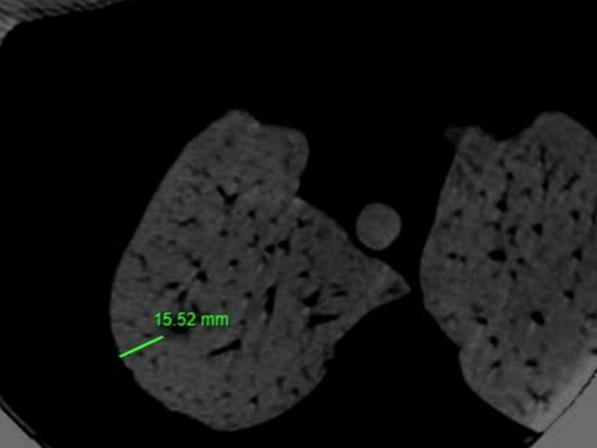

Sometimes, the identification of ground-glass opacities (GGOs), small or deep pulmonary nodules can be difficult also in expert hands. Usually for these lesions pulmonary lobectomy is an overtreatment, so we developed a technique to identify easily these nodules. The objective of this research is to assess the effectiveness and safety of using preoperative cone beam computed tomography (CBCT) to guide the placement of micro-coils in the lung parenchyma near GGO and small lesions. Additionally, the study aims to identify potential factors that could predict coil-assisted failures during uniportal video-assisted thoracic surgery (U-VATS) resections.

The clinical, radiological, and surgical records of 117 patients who underwent U-VATS resection following CBCT-guided micro-coil localization of GGOs and small deep nodules between January 2017 and February 2023 were retrospectively analyzed. We have placed a micro coil under CBCT guide before the intervention in the 24 hours preceding the intervention. The patient received a pulmonary wedge resection in U-VATS technique and an immediate fresh frozen section to determine the necessity of a pulmonary lobectomy.

One hundred and eight lesions/117 lesions (92.3%) were correctly identified by the coil. The coil placement had only mild complications: perilesional bleeding, pneumothorax requiring pleural drainage (2/117), hypotension (2/117), subcutaneous emphysema (1/117) and 1 case of coil retained in the chest wall. Ninety-seven lesions/117 lesions (82.9%) were malignant. Among these, 74 (76.3%) were lung adenocarcinomas.

有时,即使是经验丰富的医生,识别磨玻璃影(GGO)、小的或深部肺结节也可能存在困难。通常对于这些病变,肺叶切除术属于过度治疗,因此我们开发了一种能够轻松识别这些结节的技术。本研究的目的是评估术前锥形束计算机断层扫描(CBCT)引导下在GGO和小病变附近的肺实质中放置微线圈的有效性和安全性。此外,该研究旨在确定在单孔电视辅助胸腔镜手术(U-VATS)切除过程中可能预测线圈辅助失败的潜在因素。

回顾性分析了2017年1月至2023年2月期间117例在CBCT引导下对GGO和小的深部结节进行微线圈定位后接受U-VATS切除的患者的临床、放射学和手术记录。在干预前24小时内,我们在CBCT引导下放置了一个微线圈。患者接受U-VATS技术的肺楔形切除术,并立即进行新鲜冰冻切片以确定是否需要进行肺叶切除术。

117个病变中有108个病变(92.3%)被线圈正确识别。线圈放置仅出现轻微并发症:病灶周围出血、需要胸腔引流的气胸(2/117)、低血压(2/117)、皮下气肿(1/117)以及1例线圈留在胸壁的情况。117个病变中有97个病变(82.9%)为恶性。其中,74个(76.3%)为肺腺癌。